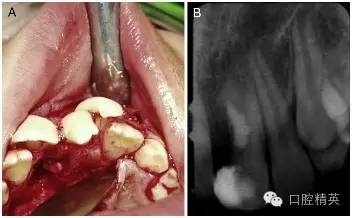

手術(shù)在局麻下進(jìn)行,無術(shù)前用藥,也沒有對(duì)口腔進(jìn)行其他特殊的術(shù)前準(zhǔn)備。為了分牙的便利,患牙唇頰側(cè)的牙齦黏膜都被切至骨膜進(jìn)行了徹底的翻瓣(圖 2-A)。

為了劈開牙冠和部分牙根,一把鋒利的骨鑿被順著牙長軸方向并稍向遠(yuǎn)中傾斜地放置在了融合牙切端的發(fā)育溝中。在錘子的猛擊下,這顆過大牙齒的多生部分被逐漸劈離出來。按照術(shù)前計(jì)劃,并通過術(shù)中調(diào)整骨鑿的傾斜度,分離的剖面最終被止于齦下。

分牙過程中,在牙根中 1/3 處出現(xiàn)了一個(gè) 4mm 范圍的橢圓形的洞,通過洞可以觀察到暴露的牙髓。牙體牙髓醫(yī)生立即用 MTA 和調(diào)拌刀對(duì)這個(gè)洞進(jìn)行了修補(bǔ)和拋光(圖 2-B)。翻瓣縫合之前,口腔外科醫(yī)生對(duì)尖銳的骨刺進(jìn)行了修整,以便縫合后的牙齦黏膜能夠與硬組織緊密地貼合在一起。

圖 2 手術(shù)過程。(A)為了方便劈牙,對(duì)唇腭側(cè)牙齦黏膜做了徹底的翻瓣。(B)多生牙部分劈開拔除后和 MTA 蓋髓后的 x 線根尖片。